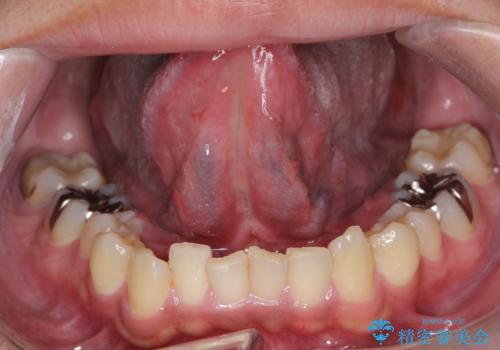

[ 舌小帯の形成術 ] ラ行の発音を改善したい

担当医 大元洋佑